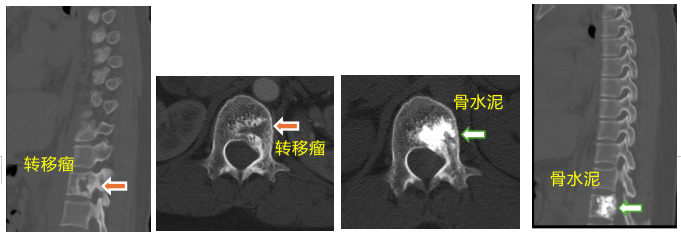

患者一、前列腺癌胸椎脊柱转移行骨水泥注射肿瘤灭活及镇痛术

患者因前列腺脊柱转移导致严重背部疼痛,行骨水泥注射后疼痛完全消失。